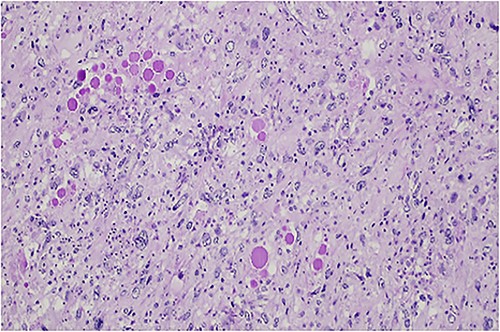

The histologic examination revealed an embryonal sarcoma (16 × 14.5 cm2) of the liver—a well circumscribed neoplasia with hyaline paucicellular areas and hypercellular areas (Fig. 4). These areas presented mainly spindle cells with severe pleomorphism as well as frequent mitotic figures, some of them atypical. Multinucleated giant cells with periodic acid-Schiff (PAS)-diastase positive hyaline globules were a habitual feature (Fig. 5) [7, 8]. Coagulative necrosis was present making up 20% of the tumor [2, 7, 8].

Hypercellular tumor showing severely pleomorphic neoplastic cells with occasional multinucleation.